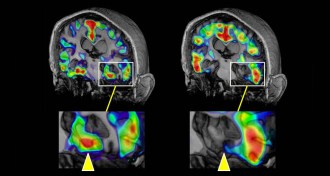

A beacon illuminates a key Alzheimer’s protein

In PET scans, researchers can now see tau, which accompanies amyloid in diseased brains.